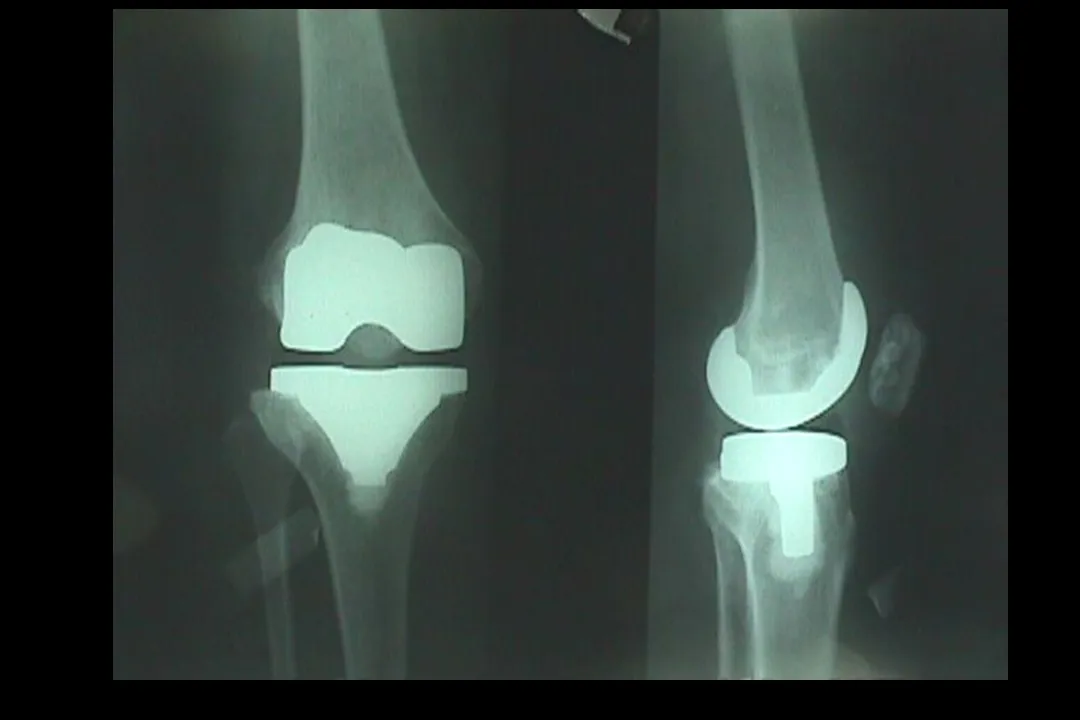

>【骨科PPT】全膝关节置换术软组织平衡

【骨科PPT】全膝关节置换术软组织平衡